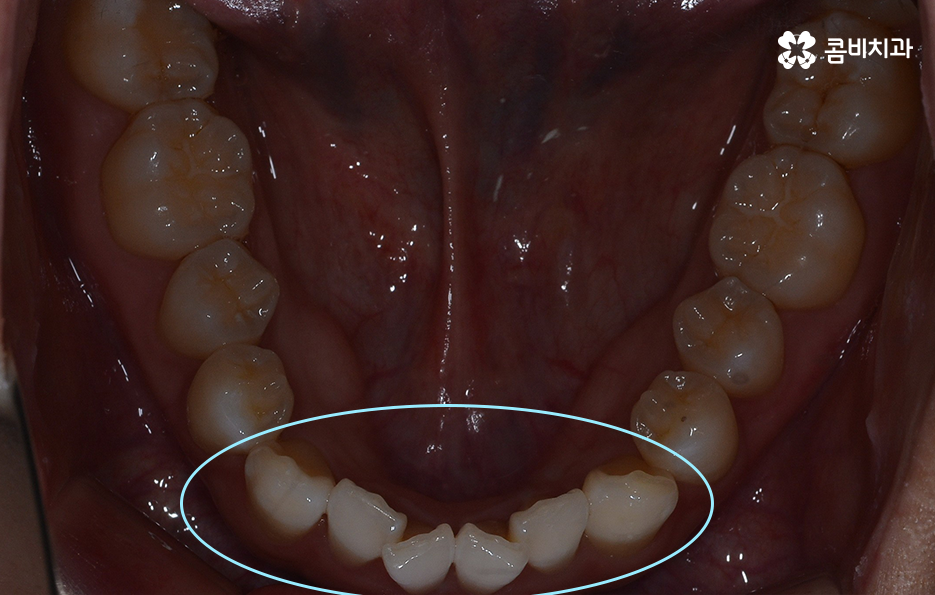

이 중에서는 발치 여부에 대해서도 많은 고민이 되는 부분 중에 하나일 거예요. 교정 치료에서 발치를 하는 경우에는 보통 작은 어금니를 발치하여 치아의 이동 공간을 확보하는 경우가 많은데 아무래도 생니를 발치한다는 생각에 발치는 무조건 안좋다고 느끼거나 거부감을 느끼시는 분들도 많이 있어요.

교정 치료는 크게 발치와 비발치치아교정으로 나뉠 수 있는데 비발치치아교정의 경우에는 아무래도 치아가 움직이는 양도 적고 그에 따라 교정 기간도 짧은 편에 해당되고 있어요.

단순히 비발치치아교정이 발치를 안해도 되니 무조건 좋다고 판단하기 보다는 각 개인의 치료 목적과 구강 및 골격, 얼굴형의 상태를 종합적으로 정밀 검진하여 자신에게 적합한 치료 계획을 잘 세우는 것이 중요하다고 강조드리고 있어요